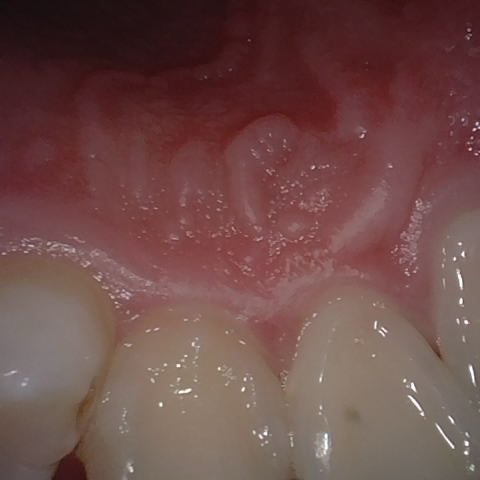

Annotated as "Good"